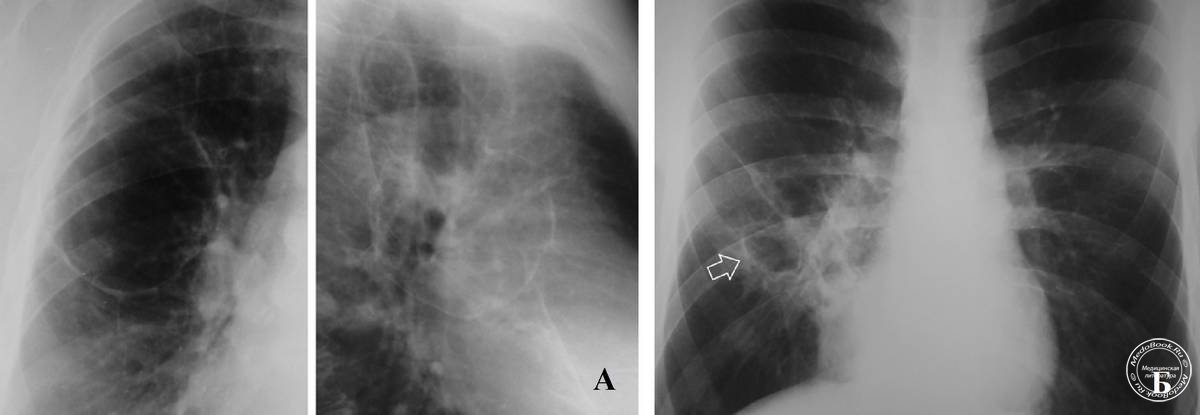

Рентгеновские снимки при врожденной эмфиземе легкого

Раздел: Визуальные уроки